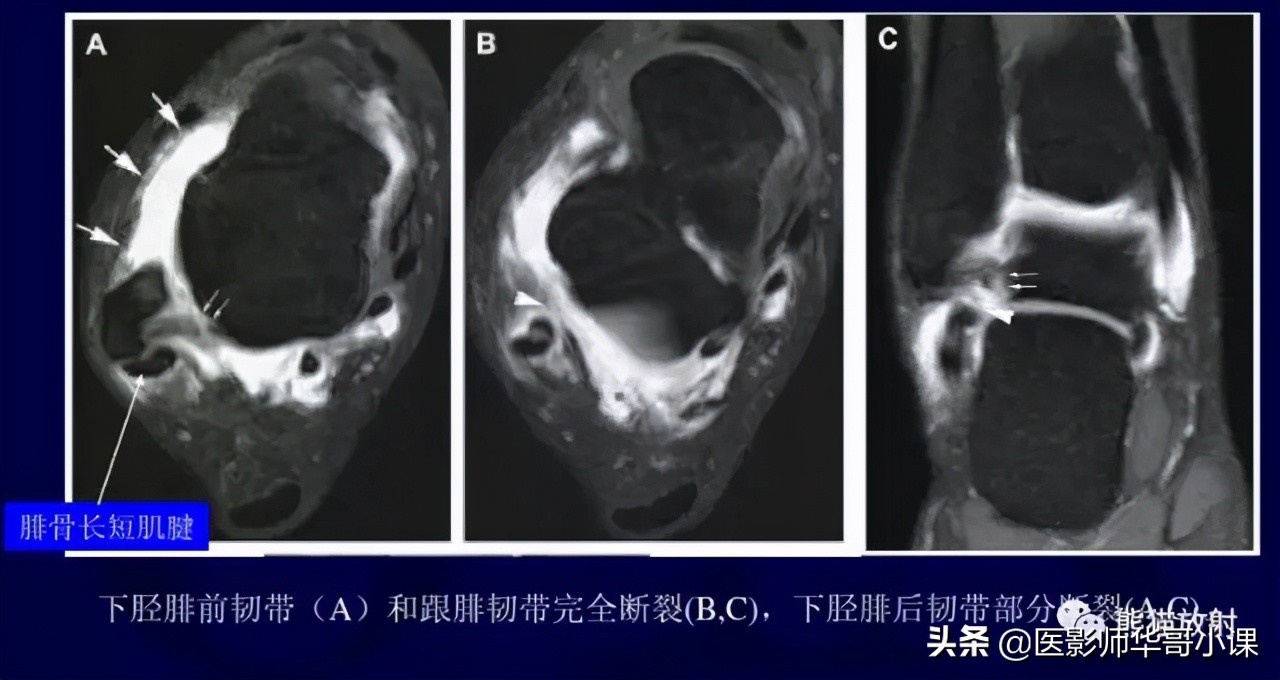

下胫腓联合韧带

胫腓骨远侧关节面由腓骨远端的凸面和胫骨远端的凹面组成,由胫腓韧带链接,关节内无软骨结构。 远端胫腓联合韧带由四部分韧带组成,包括: 骨间韧带,下胫腓前韧带,下胫腓后韧带,下横韧带。

骨间韧带由骨间膜远端增厚形成。下胫腓前韧带起于胫骨结节的前外侧,止于腓骨脊的前侧。下胫腓后韧带起于胫骨脊后侧,止于外踝后缘。下横韧带组成下胫腓后韧带的下半部分,可视为下胫腓后韧带的一部分。

下胫腓前韧带(35%),下胫腓后韧带深层(33%)对踝关节稳定性作用最大,其次是骨间膜(22%)和下胫腓后韧带浅层(9%)。

下胫腓联合韧带损伤的机制 通常是踝关节外旋和过度背屈。可以导致下胫腓联合损伤的运动包括运动(足球等),低能量创伤等。外旋损伤通常发生于踝关节旋前或旋后位。胫腓联合韧带损伤可以单发或者合并骨折。

下胫腓联合远端韧带结结构,包括:骨间韧带(IOL),下胫腓前韧带(AITFL),下胫腓后韧带(PITFL),下横韧带(ITL)。